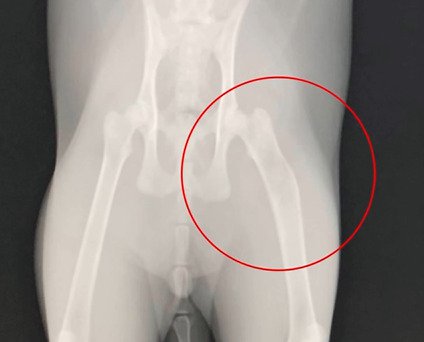

子猫を緊急保護して病院で診てもらったところ、左脚骨折、内臓損傷など酷い状態で、命が1週間保つかどうか…というほど瀕死だったそうです。主さんは「短い時間しか一緒にいられない」と悲しい思いをしながらも、残り少ないであろう時間を子猫と共に過ごすことを決めたといいます。

左脚の骨がくっついた